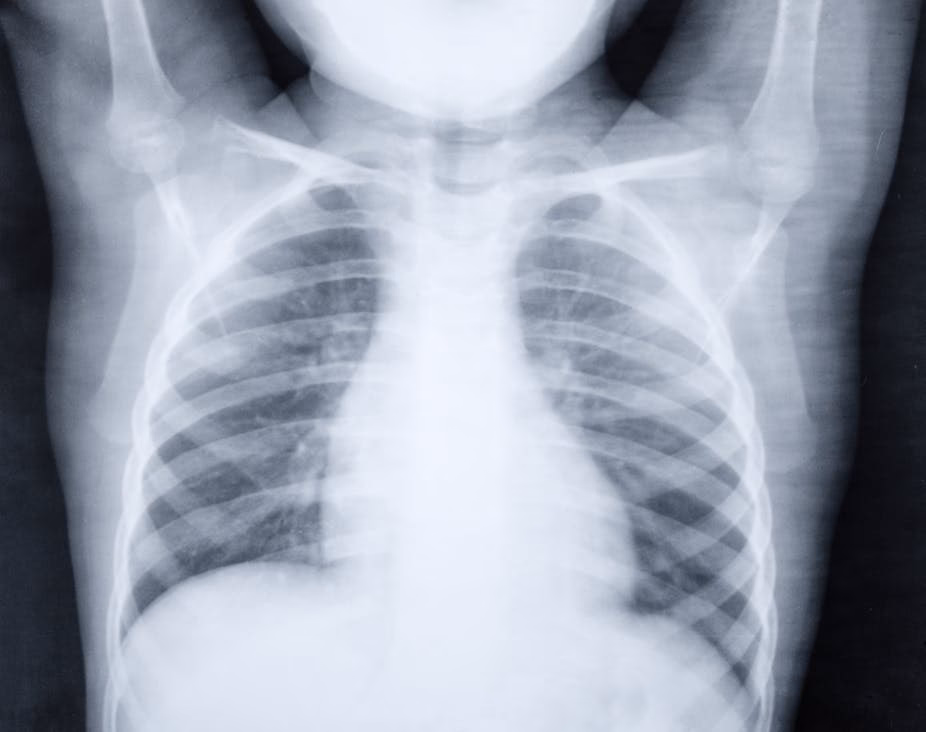

Lungebetændelse, på latin kaldet pneumoni, er en infektion i en eller begge lunger. Vores lunger består af millioner af små luftsække, kaldet alveoler. Når vi trækker vejret, fyldes disse sække med luft. Hos et barn med lungebetændelse bliver disse luftsække betændte og fyldes med væske eller pus. Dette gør det sværere for ilten at komme over i blodet, hvilket kan føre til de karakteristiske symptomer som hoste og åndedrætsbesvær. Infektionen kan ramme et lille område af lungen eller sprede sig til større dele af en eller begge lunger.